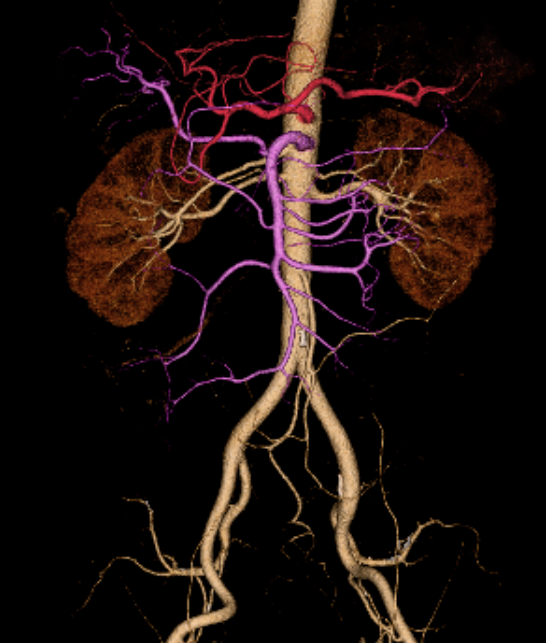

術前シミュレーション画像(CT画像)

術前の検討